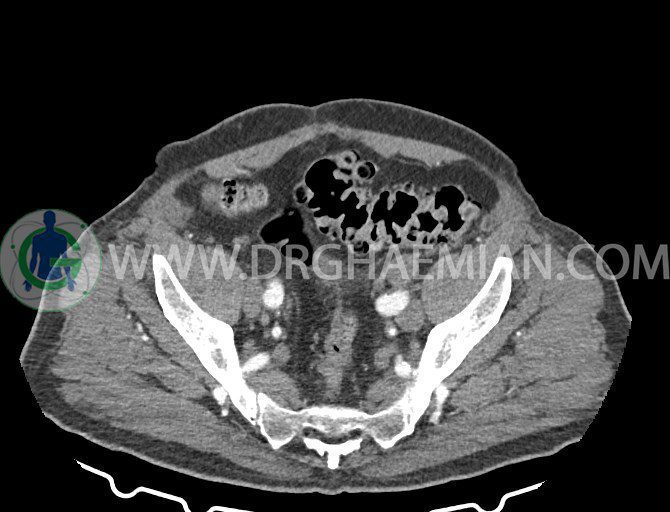

سی تی اسکن لگن یکی از روش های تصویربرداری با سی تی اسکن است. این روش با استفاده از تشعشعات تصاویر عرضی از ناحیه شکمی ایجاد میکند. در این کیس ديورتيكولوزيس، کیست های کورتیکال در هر دو کلیه، لنفادنوپاتی، کلسیفیکاسیون دیواره آئورت و شریان ایلیاک، تغییرات DJD ناحیه توراکولومبار و پروستات بزرگتر از عادی دیده می شود.

در سي تي اسکن اسپيرال شکم و لگن با و بدون کنتراست خوراکی و وريدی (مولتي ديدکتور 16 با مقاطع ظريف و بازسازي هاي ساژيتال و کرونال):

– کلسيفيکاسيون ديواره آئورت و شريان ها ايلياک همراه با نشانه هاي ترومبوز مورال در بيفورکاسيون ائورت با امتداد به پروگزيمال هاي شريان هاي ايلياک

لنفادنوپاتي به ابعاد mm 22 x 25 مجاور شريان ايلياک خارجي چپ و به ابعاد mm 17 x 28 مجاور شريان ايلياک خارجي راست